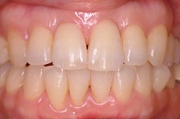

CASE3

前歯1本だけが出ています、矯正で治りますか?

(23歳/女性)↓

||||||||

概要・担当医コメント:

前歯の唇側傾斜/マルチブラケット装置/非抜歯

動的治療期間15ヶ月(15回)/費用概算:60万円.

歯列アーチの形態修正に必要なスペースを微量のエナメル質の研磨により創生し,当初の計画通りに歯を移動させました.